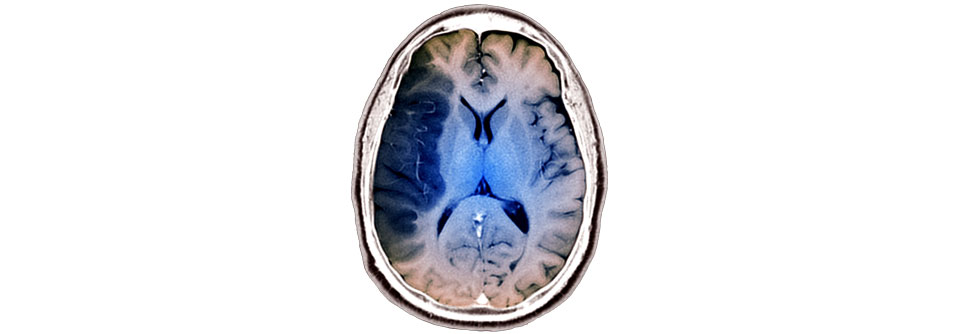

Links im Bild: Dieser ischämische Infarkt der A. cerebri media ist nach fünf Stunden gut erkennbar. (Agenturfoto) Links im Bild: Dieser ischämische Infarkt der A. cerebri media ist nach fünf Stunden gut erkennbar. (Agenturfoto) © Science Photo Library / Zephyr; highwaystarz – stock.adobe.com

Patienten mit akutem ischämischen Insult werden nach Ausschluss von Kontraindikationen (z.B. gerinnungshemmende Medikation) üblicherweise mit einer intravenösen Thrombolyse (IVT) behandelt. Diese Therapieform wirkt bei über 80-Jährigen ebenso gut wie bei jüngeren Patienten. Das Zeitfenster für die IVT schließt sich normalerweise nach viereinhalb Stunden. Wenn  seit Symptombeginn viereinhalb bis neun Stunden vergangen sind oder Unklarheit über den Zeitpunkt des Insults herrscht, kann eine erweiterte Bildgebung mittels CT- oder MR-Perfusion erfolgen, um die Indikation für die Lyse stellen zu ­können.